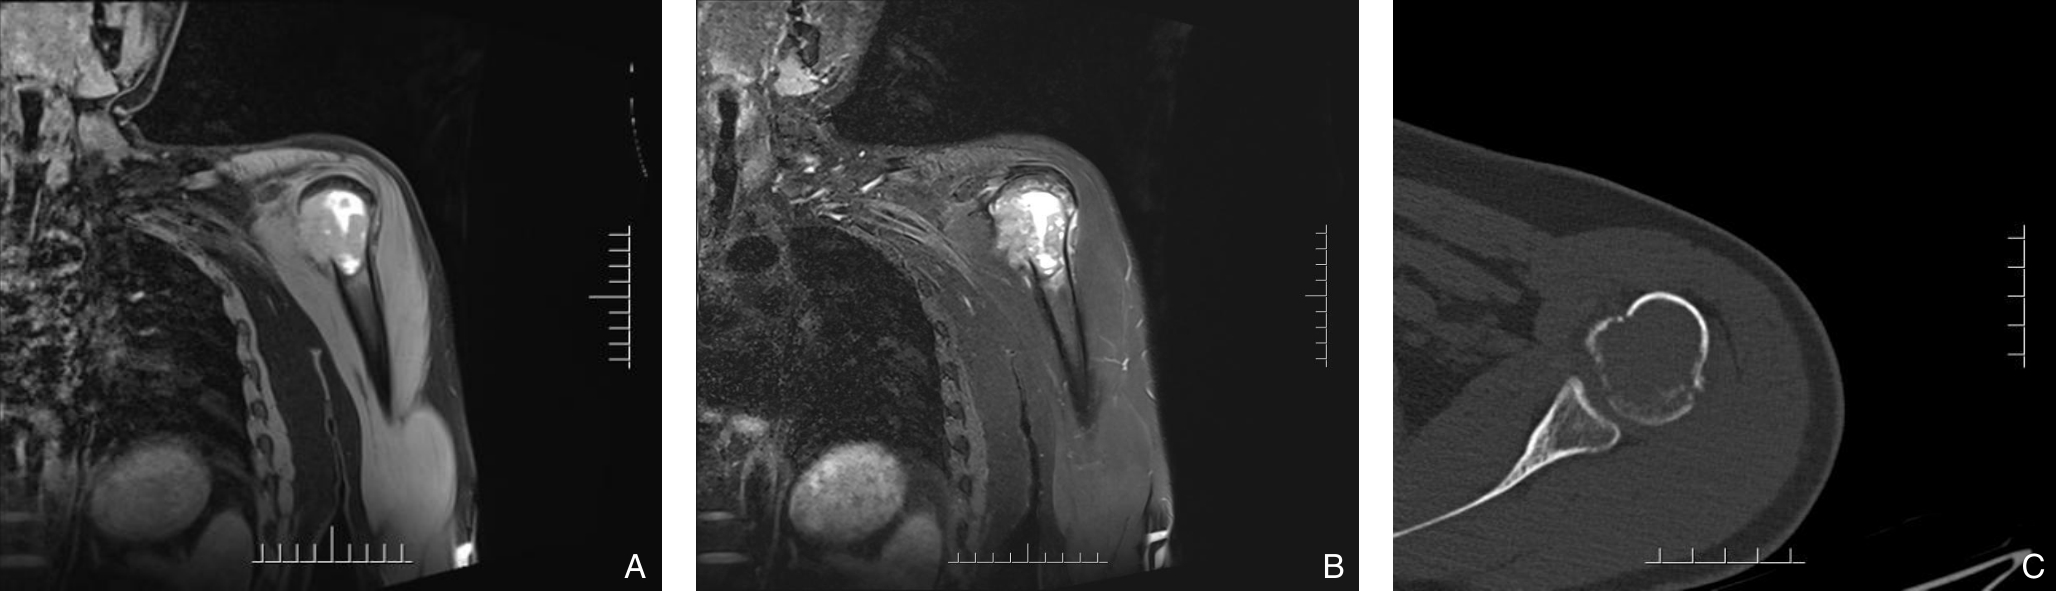

Background and Aims Hepatocellular carcinoma (HCC) presenting initially with bone metastasis is uncommon, and metastasis to the appendicular skeleton is particularly rare. These cases often lack typical liver disease history, elevated alpha-fetoprotein (AFP), or characteristic imaging findings, leading to frequent misdiagnosis or delayed diagnosis. This study reports a rare case of occult HCC presenting with humeral metastasis and reviews the literature to improve clinical recognition and management.Methods The clinical data of a 42-year-old male patient presenting with humeral metastasis as the initial manifestation admitted in August 2025 were retrospectively analyzed, including laboratory tests, multimodal imaging findings, histopathological and immunohistochemical results, treatment, and follow-up outcomes. Relevant literature was also reviewed.Results The patient presented with left shoulder pain. Imaging revealed osteolytic destruction of the left humerus. PET/CT incidentally detected multiple hepatic lesions without significant FDG uptake. Contrast-enhanced ultrasound demonstrated atypical enhancement patterns, initially suggesting a perivascular epithelioid cell tumor. Histopathological and immunohistochemical examination of biopsy specimens from both the humeral and hepatic lesions confirmed moderately differentiated hepatocellular carcinoma with humeral metastasis (CNLC stage IIIb). The patient received systemic therapy with sintilimab plus bevacizumab, followed by transcatheter arterial chemoembolization. After 6 months of follow-up, the intrahepatic lesions had decreased in size, the bone metastasis remained stable, and pain symptoms were significantly relieved.Conclusion HCC presenting with humeral metastasis as the initial manifestation is extremely rare and may lack typical imaging and serological features. Clinicians should consider HCC in patients with unexplained bone metastasis even in the absence of liver disease history or elevated AFP. Multimodal imaging and pathological biopsy are essential for accurate diagnosis and appropriate management.